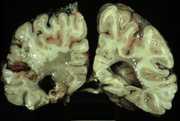

12